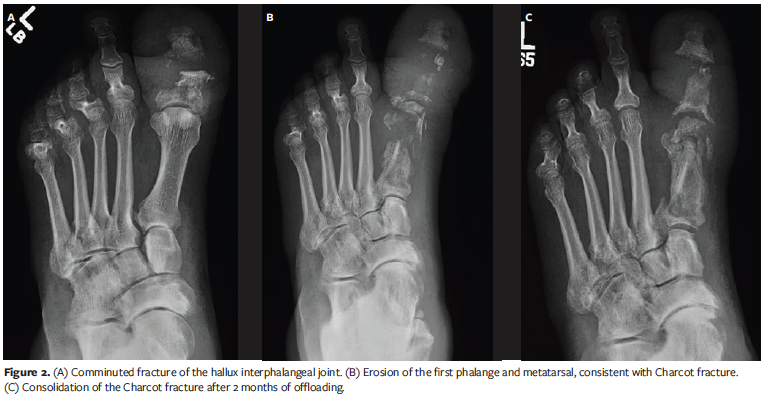

After the ulcer healed, a left hallux interphalangeal arthroplasty was performed. The patient was instructed to ambulate with a surgical shoe and walking cane, only putting weight on the heel. One month after surgery, he developed a dehiscence, approximately 0.4 cm × 2 cm in size, with no clinical signs of infection. He was treated and instructed to offload. The dehisced wound healed in 2 months. The patient presented 3 months later with swelling and redness of the foot. He had no ulcer and denied any trauma. Radiographs showed a comminuted fracture of the hallux interphalangeal joint (Figure 2A). The radiographic reports did not mention OM or CN. He was placed in a CAM boot and instructed not to bear weight on the foot. The patient returned in 2 weeks, but the swelling had not improved. Repeat radiographs at this visit showed more bone fragments of the left hallux proximal phalange and first metatarsal concerning OM (Figure 2B). The current study’s authors maintained that the changes were consistent with CN rather than OM and continued to treat the patient with offloading and a CAM boot. He was scheduled to follow up every 2 weeks and was advised to return sooner if there was a wound. The swelling subsided after 2 months, and new radiographs showed consolidation of the fragmented bone (Figure 2C).